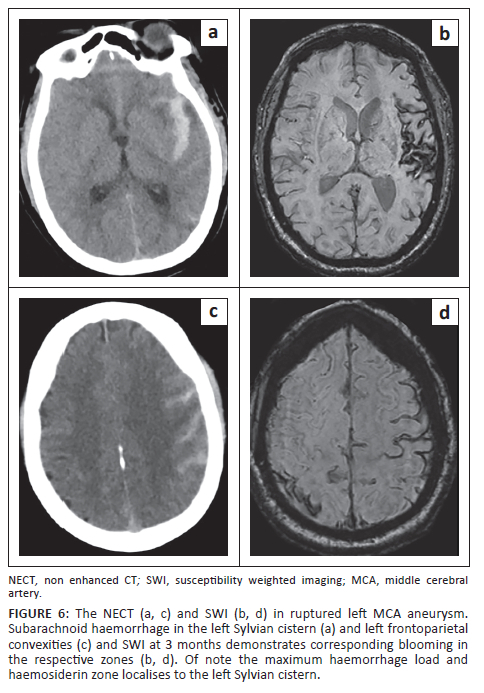

Maximum haemosiderin staining in the Sylvian cisterns was seen with ipsilateral middle cerebral (PPV = 31.25%), posterior communicating (PPV = 50%) and distal internal carotid arteries aneurysms (PPV = 18.75%) and hence was not specific for ruptured MCA aneurysms as observed in previous studies in the acute phase.21,22,23,24 This is thought to be related to CSF flow dynamics and deposition of haemosiderin. Figure 6 demonstrates an example of localised haemosiderin and haematoma related to the Sylvian fissure.